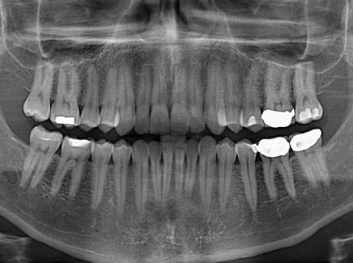

損壞的牙齒如何自我修復(fù)?近日,來自哈佛大學(xué)和諾丁漢大學(xué)的研究人員研發(fā)了能夠刺激牙齒干細(xì)胞再生的新型生物材料,而這種新材料研發(fā)成功的背后,正源于他們對(duì)牙齒如何實(shí)現(xiàn)自我修復(fù)這個(gè)課題的不斷探索。

據(jù)美國期刊《大眾科學(xué)(Popular Science)》報(bào)道,此種新型生物材料,不僅可以有效地取代傳統(tǒng)補(bǔ)牙填充物,刺激牙齒干細(xì)胞再生,患者也有望無需再接受根管治療,使蛀牙患者免除牙根感染或牙髓壞死的苦惱,一個(gè)全新的牙齒治療時(shí)代即將來臨。

Adam Celiz,是來自諾丁漢大學(xué)的研究人員,他和同事開發(fā)的這種新型合成生物材料,能刺激干細(xì)胞在牙髓部的生長。與普通材料一樣,這種合成材料被填充到牙齒并用UV光硬化。

在體外測試中,材料刺激干細(xì)胞進(jìn)入牙本質(zhì)的增殖和分化速度,促進(jìn)形成牙齒骨組織。研究人員認(rèn)為,一旦材料在受損牙齒中應(yīng)用,這些干細(xì)胞可以自動(dòng)修復(fù)來自填充物上的損壞。在本質(zhì)上,該生物材料將使牙齒自愈。

在未來,Adam Celiz說,可再生材料能制成各種填充物以便受損牙齒的自身治愈,降低補(bǔ)牙失敗率,甚至?xí)蟛糠秩藢?duì)根管治療的需要。